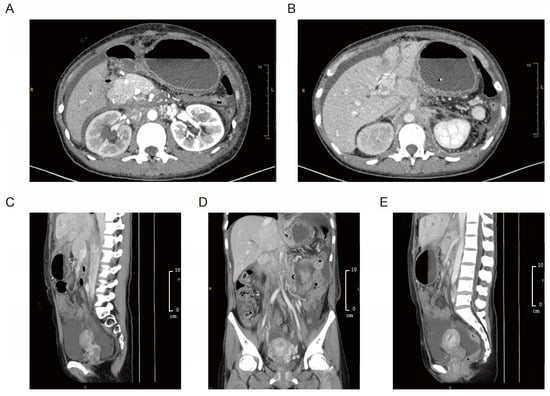

CT revealed absence of the inferior vena cava, polysplenia, intrahepatic ductal dilatation, thickening of the gastric fundus, and a mass in the retroperitoneal region. Subsequent magnetic resonance cholangiopancreatography (MRCP) and computed tomography angiography (CTA) showed thrombosis of the left portal vein, congenital pancreatic hypoplasia, and peripancreatic space-occupying lesions. Compression of the duodenum by a congenitally enlarged pancreatic head, stricture of the hepatic portal bile duct, dilation of the level-two and level-three bile ducts on the right side, and thickening with enhancement of the bile duct wall were also confirmed. Contrast-enhanced CT and repeated MRCP upon referral revealed duodenal compression by an enlarged pancreatic head, hepatic bile duct strictures, and thickened, enhancing bile duct walls suggestive of obstruction (Figure 1). PET-CT demonstrated only mildly elevated metabolic activity in lesions around the ligamentum teres hepatis, which was not sufficient to establish a definitive diagnosis of malignancy.

Figure 1. Imaging findings of retroperitoneal fibrosis with peripancreatic and hepatic involvement of the patient. (A,B) Abdominal contrast-enhanced CT revealed duodenal compression by a congenitally enlarged pancreatic head, stricture of the hepatic portal bile duct, and dilation of second- and third-order bile ducts on the right. The bile duct wall appeared thickened with contrast enhancement. (CE) Coronal and sagittal contrast-enhanced CT demonstrated thickening and enhancement of the bile duct wall. Space-occupying lesions in the retroperitoneal and peripancreatic regions extended toward the round ligament of the liver, exhibiting a fibrosis-like appearance rather than a well-defined mass.